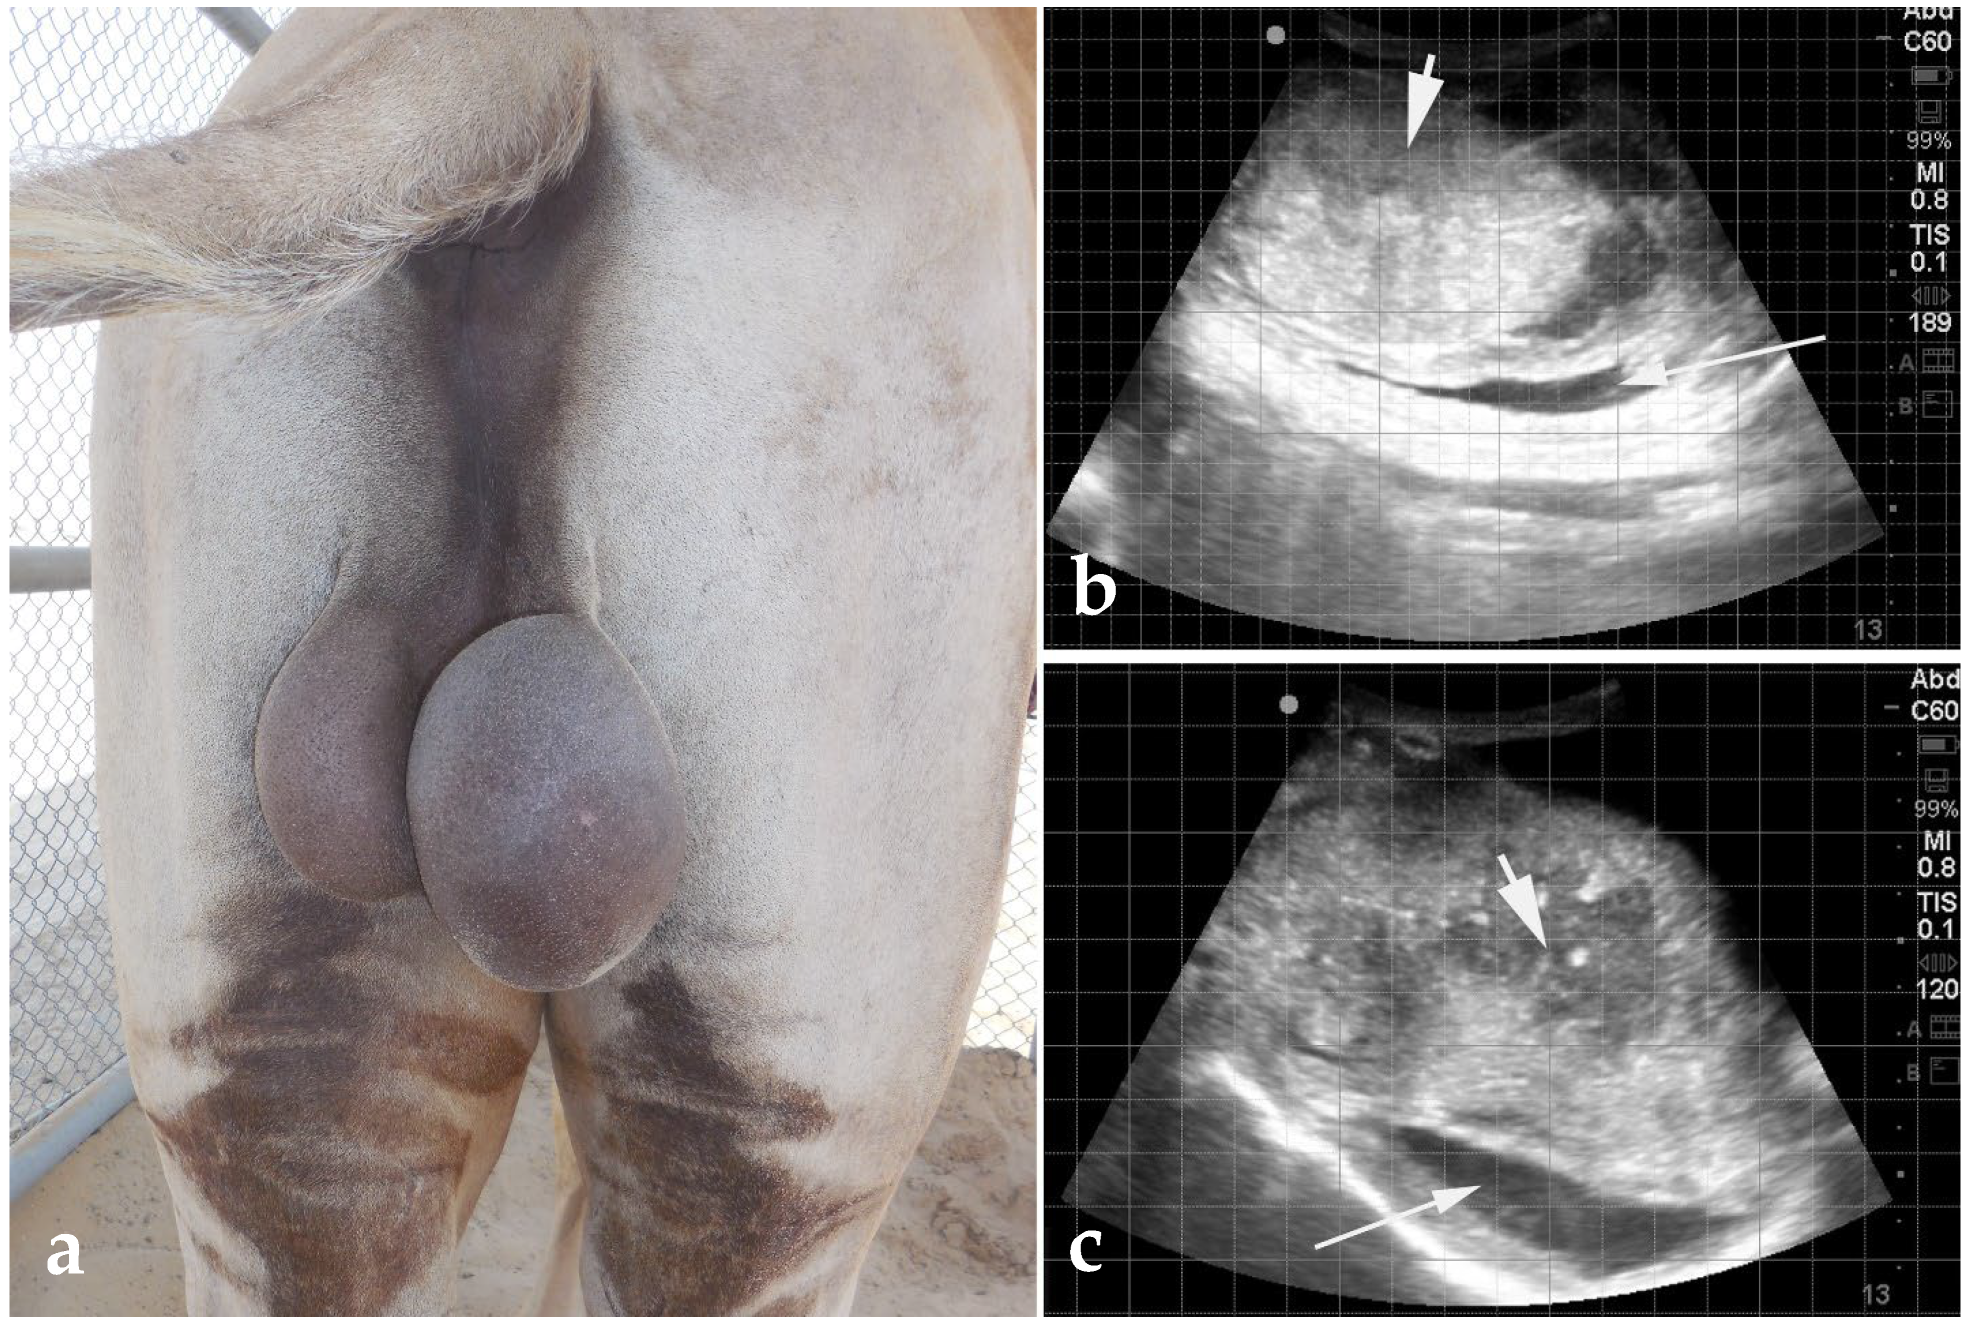

6.1. Scrotal Enlargement

3.1. Cryptorchidism